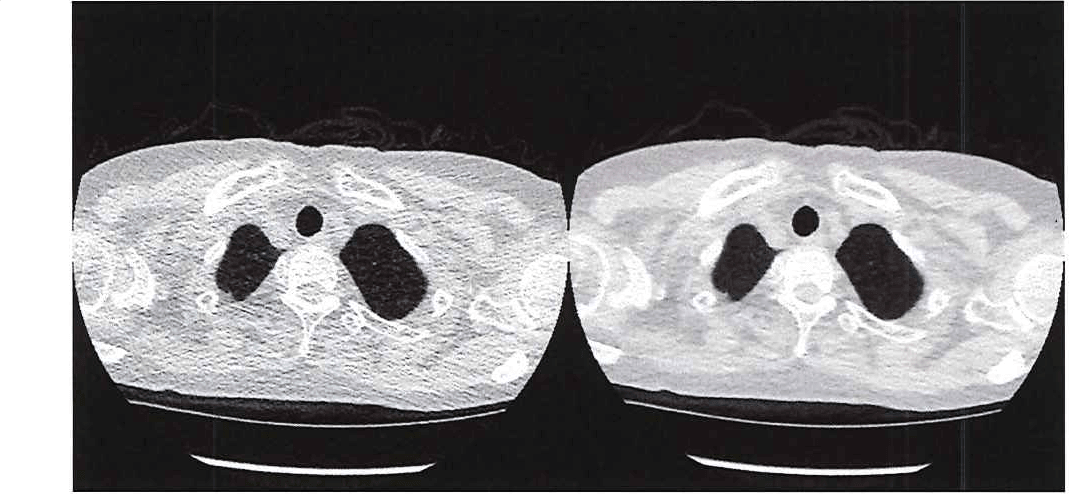

Because they produce 3D images of organs, bones, and blood vessels, computed tomography (CT or CAT) scans have significantly greater diagnostic value than simple X-rays. This added diagnostic value, however, comes at a cost: increased exposure to potentially harmful radiation. The 3D images produced by a CT scan are assembled from 2D X-ray images stacked together by computer software. As a result, a single CT scan of the chest has an average effective radiation dose of 7 milliseverts (mSv), 350 times higher than the chest X-ray dose of 0.02 mSv. [1] Radiation exposure is correlated with cancer risk; guidelines limit the radiation dose to 1.5 mSv in CT scans of children. Medical researchers want to limit radiation exposure while providing physicians with the image clarity they need. One promising approach is the use of ultra-low-dose CT, which has an effective average dose of about 0.13 mSv for a chest image. [1] The principal drawback of ultra-low-dose CT scans is their relatively low resolution and high level of noise, which can make it difficult for physicians to see organs, fat, and interstitial tissue (Figure 1). Figure 1. Comparing the image quality of ultra-low-dose CT (left) with a traditional CT (right). I have developed a MATLAB® software system based on convolutional neural network (CNN) regression that uses ultra-low-dose CT scans as input but generates images comparable in quality to a normal-dose CT scan. The system provides physicians with a comparable level of diagnostic information while reducing patient radiation exposure by as much as 95%. Super-Resolution vs. CNNsWhen I began researching ways to improve the quality of low-dose CT images, I applied a super-resolution technique in which I used MATLAB to divide CT images into small local regions and then paired low-dose and normal-dose regions to create an image dictionary. When a new low-dose image is to be analyzed, the system finds a small low-dose region in the dictionary and presents the corresponding normal-dose patch to the user. The technique’s effectiveness depends on having a huge dictionary from which to draw comparisons. However, increasing dictionary size increases the resource demands of the system and, more importantly, the search time needed to find small images. While a CNN takes time to train, when presented with a new image it produces results much faster than the super-resolution approach I developed. For example, a trained CNN can yield results in about 20 minutes for a single patient, whereas it took about 2 hours to obtain comparable results using super-resolution. Although I began exploring CNN regression to address the shortcomings of super-resolution, there are some cases in which the super-resolution technique performs very well. For example, when patterns in an image to be diagnosed closely resemble those in one of the dictionary images, the super-resolution approach produces highly accurate results. For this reason, I plan to create a hybrid system that combines CNN regression with super-resolution. Obtaining Images and Constructing the CNNsTo improve the clarity of ultra-low-dose chest CT scans, I applied an approach that uses two CNNs, one targeting the lung areas of the CT images and the other targeting the non-lung area (Figure 2). The image data set that I used to train the CNNs was provided by researchers at Mie University. It consists of 12 image pairs, each of which includes a normal-dose scan and an ultra-low-dose scan of the same tissue. (Because taking a second image means exposing a patient to additional radiation, we had to limit the study to a relatively small subject pool.) Each image in the study was 512 x 512 pixels, and each scan contained 250 images (slices).